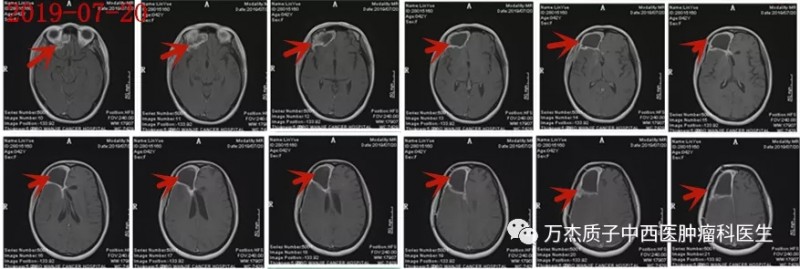

2019-07-20手术后MR: 术后需照射区域巨大